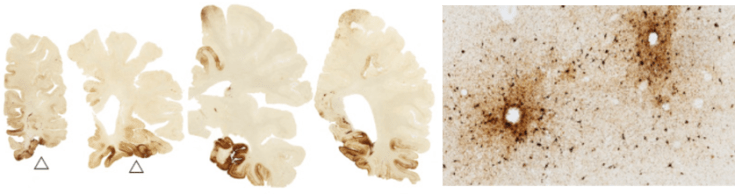

Other degenerative diseases also have tangles of tau, the most well-known of which is Alzheimer’s disease (AD). So how are AD and CTE different? A major difference is the location of the tau tangles within the brain. In AD, tangles are found early and abundantly in a region of the brain called the hippocampus3. This area is important for certain kinds of memory, which is why patients with AD have primarily memory issues. In contrast, in CTE the tau tangles are found mainly in clusters in the cerebral cortex, particularly in the depths of the grooves of the brain (called sulci), and often around blood vessels2 (Figure 3).

Figure 3: Image reproduced from McKee, A.C. & Robinson, M.E. Miltary-related traumatic brain injury and neurodegeneration. Alzheimers. Dement. 10, S242-53 (2014). CC BY-NC-ND 3.0